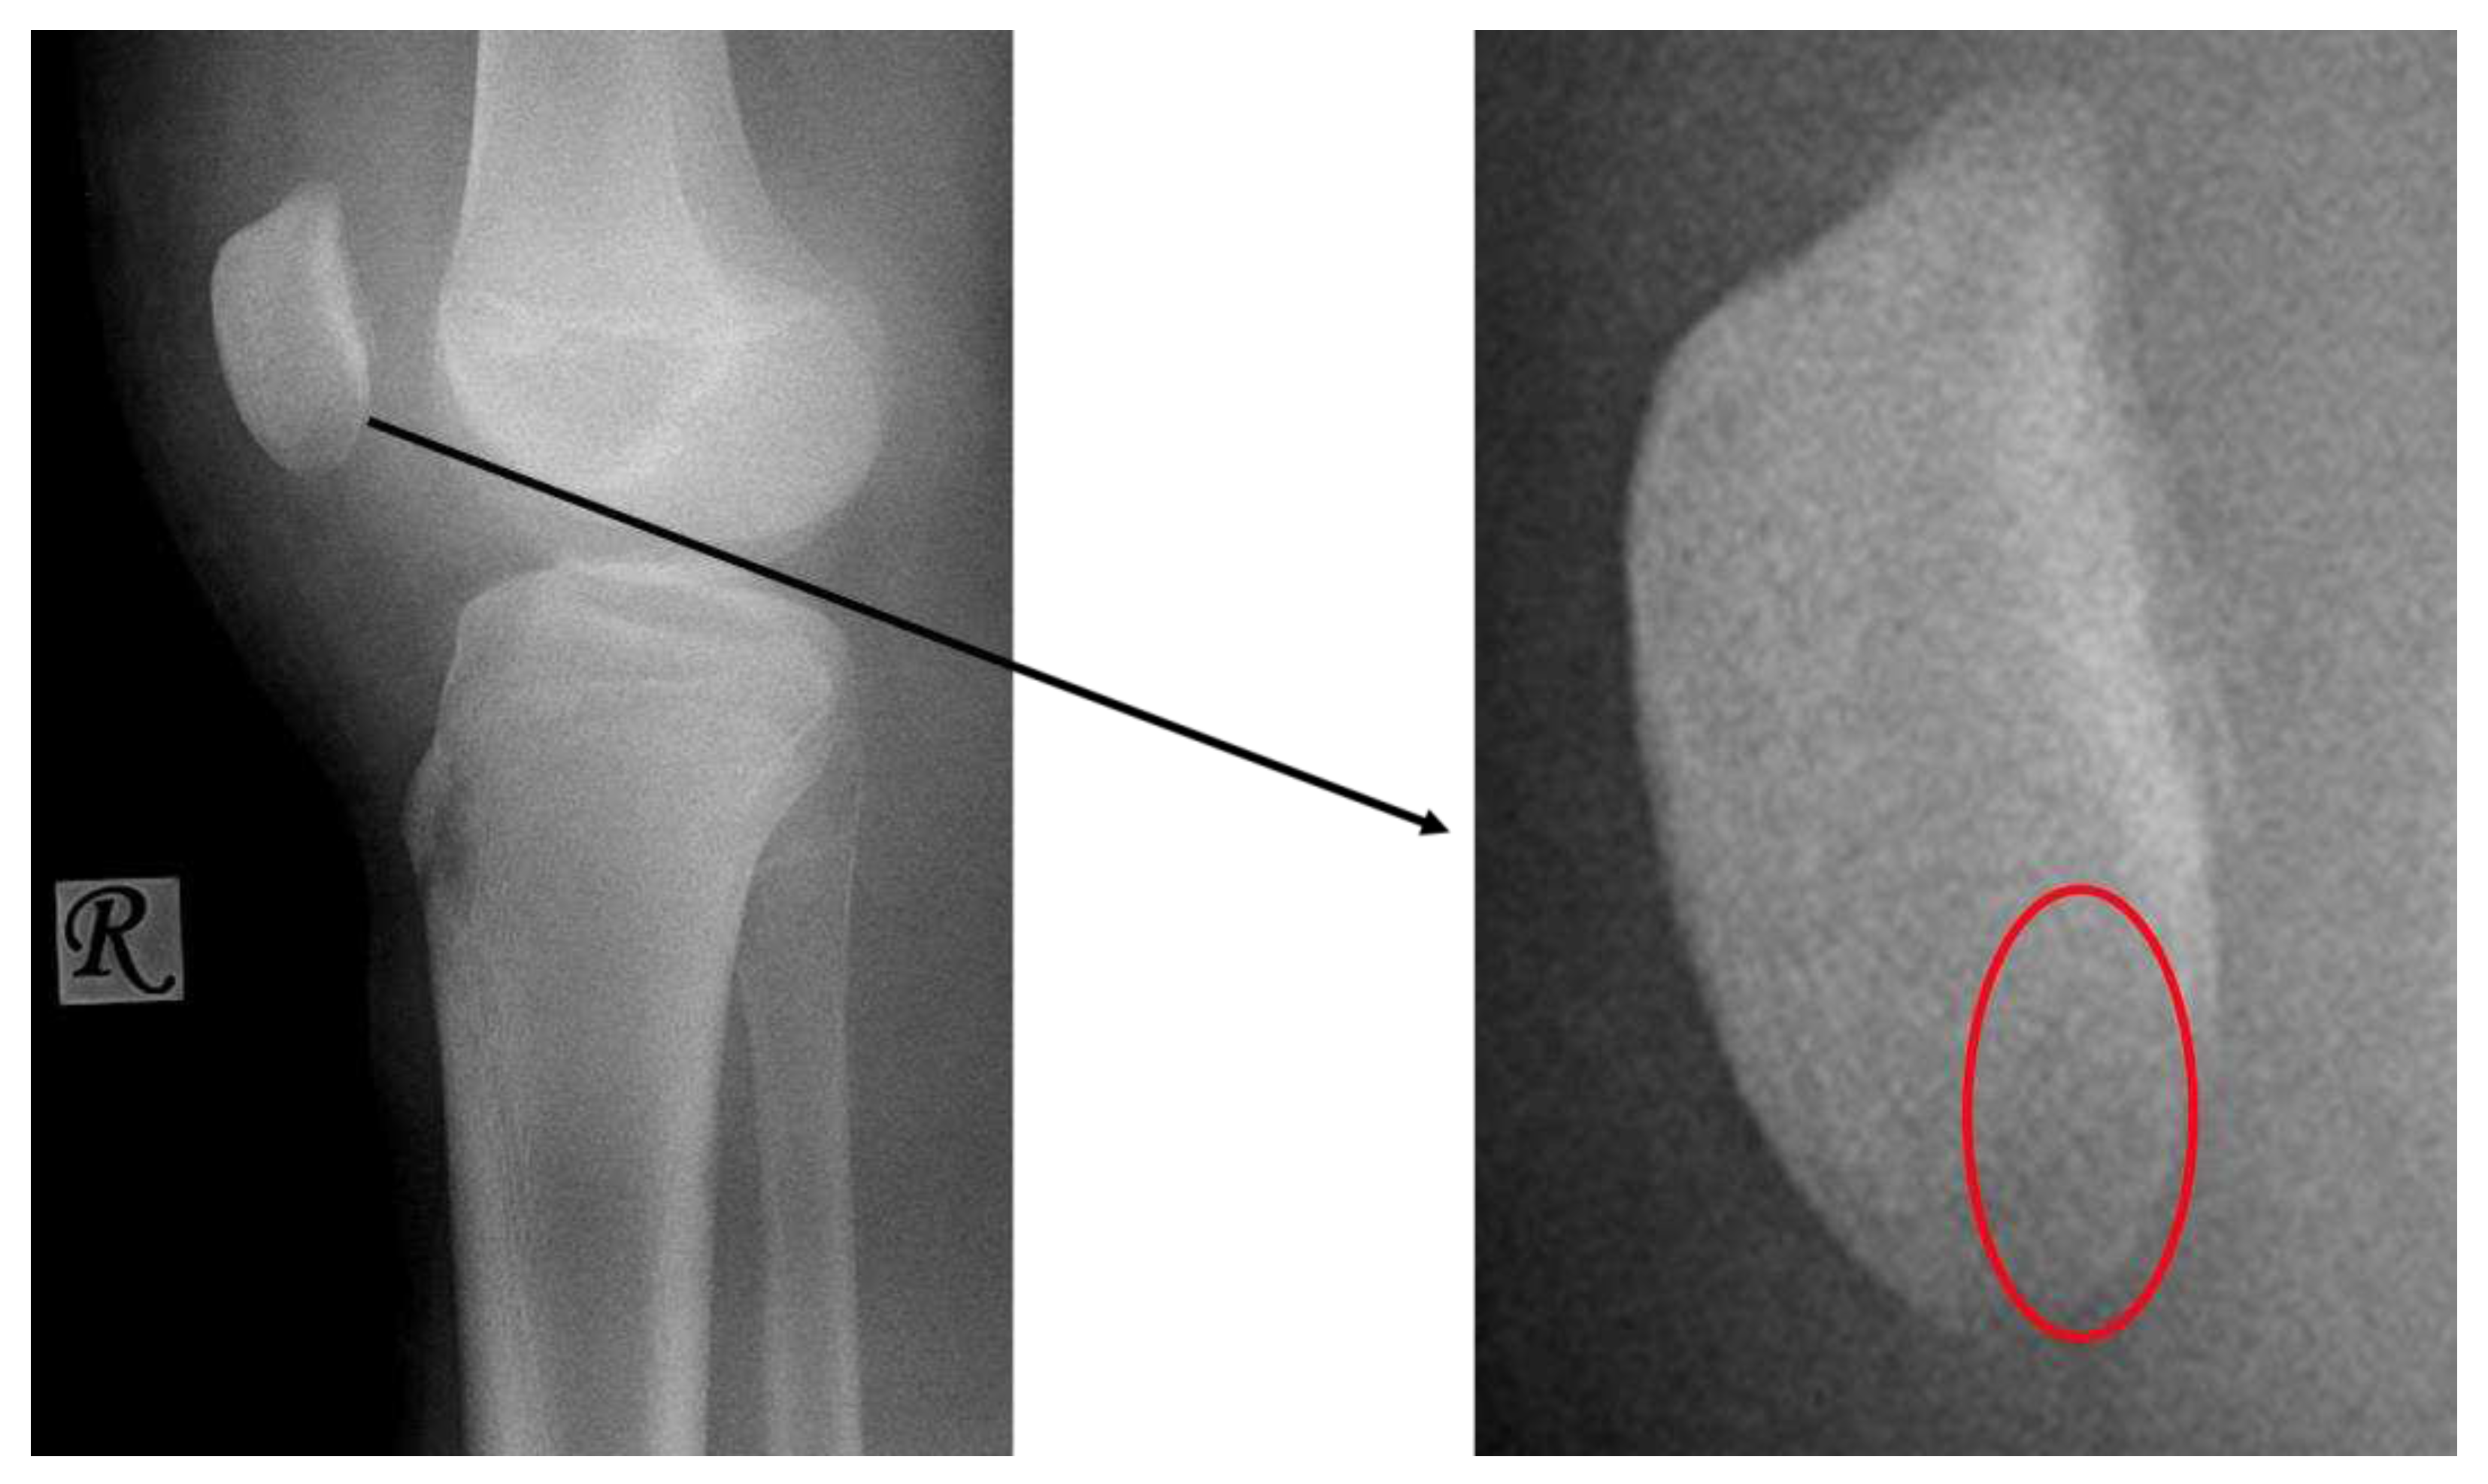

- X-ray: Lucency between fragment and normal bone.

- X-ray: Loose body, lucency